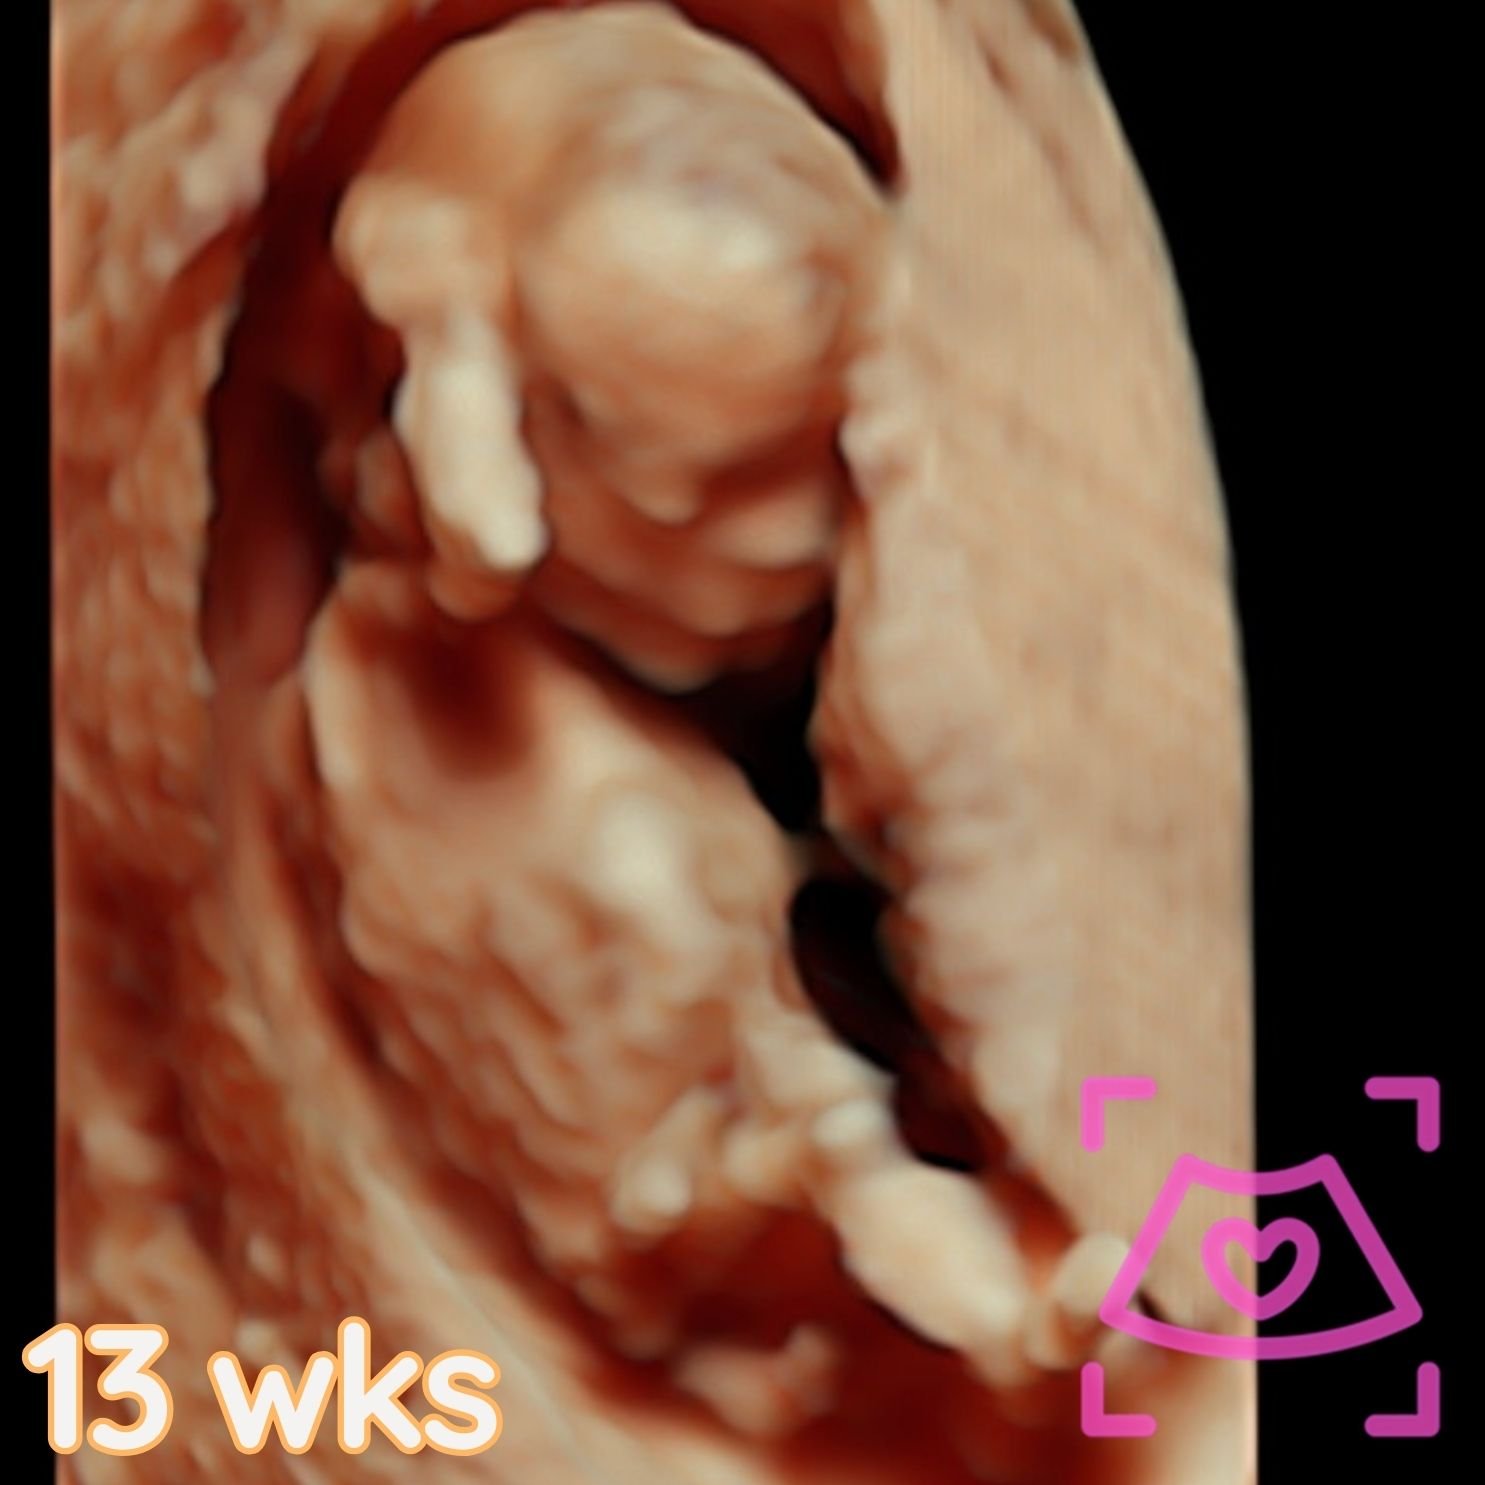

All ultrasounds at this facility are performed abdominally (on top). See examples below from 5-40 weeks! Recommended times can be found on the Services Page and when booking.

1st Trimester